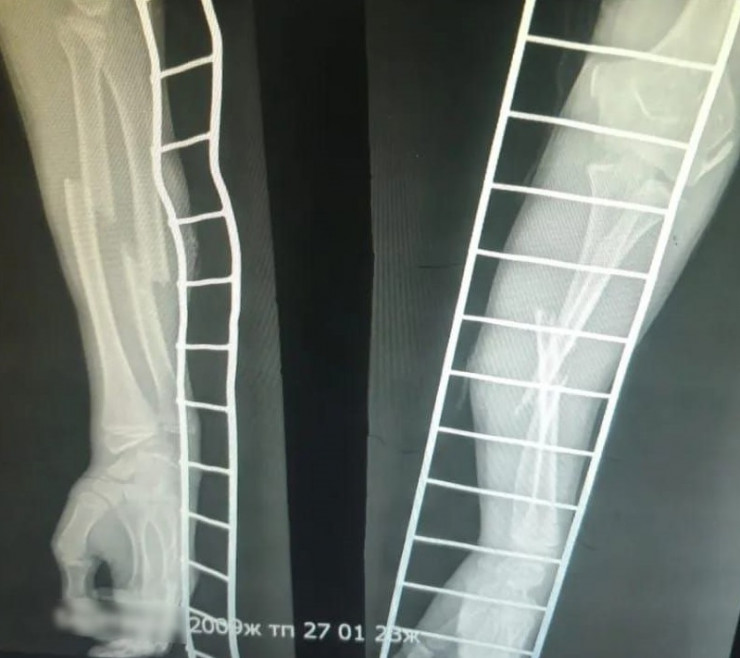

Общественный деятель Дина Тансари сообщила, что у пострадавшего школьника были сломаны две кости. При этом уголовное дело против обидчика не завели, так как он не достиг 14 лет. Также дело не направили в суд по статье 140 УК РК в отношении родителей за "Неисполнение обязанностей по воспитанию несовершеннолетнего".

Фото: t.me/dina_tansari